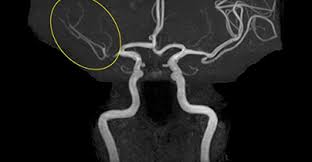

- MRA (자기공명혈관조영술): MRI 원리를 적용해 **혈관 내부 구조와 혈류 흐름**을 3D 영상으로 확인하는 검사입니다. 동맥류, 혈관 협착·폐쇄·혈전 등의 진단에 사용됩니다 :contentReference[oaicite:2]{index=2}.

| MRA | 혈관(동맥·정맥) | 뇌혈관 질환, 동맥류, 혈관 협착·폐쇄, 혈전 |

- MRA 장점: 혈관 질환(협착, 동맥류 등) 진단에 특화, **비침습적이고 방사선 노출 없음** :contentReference[oaicite:9]{index=9}.